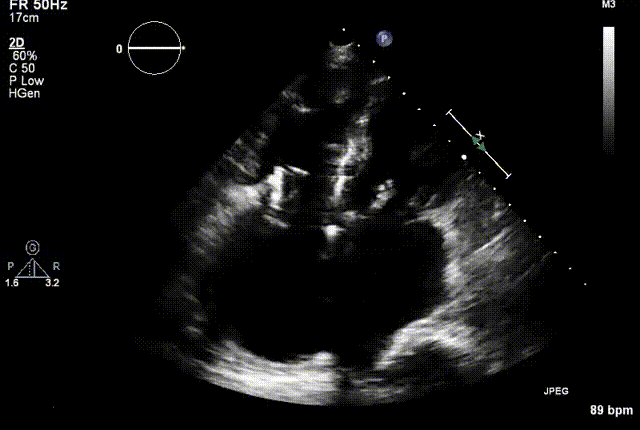

2021年12月7日,复旦大学附属中山医院葛均波院士团队完成的首批两例LuX-Valve Plus经血管三尖瓣置换患者顺利出院,从患者入院至出院仅历时一周时间,出院时患者状态恢复良好,复查心超三尖瓣无反流。

两例患者是都是外科手术高危的极重度三尖瓣反流的老年女性,反复下肢水肿、腹胀、纳差,活动耐力减退。一例患者风湿性心脏病,二尖瓣生物瓣置换术后,房颤,心超显示三尖瓣极重度反流(最大反流宽度15mm);另一例患者房颤,心超示三尖瓣极重度反流(最大流宽度23mm)。

结合术前CT评估结果,葛均波院士团队最终决定选用LuX-Valve Plus 50mm和55mm两种型号的瓣膜,并于2021年11月30日顺利完成LuX-Valve Plus经血管三尖瓣置换术,手术室即刻拔除气管插管,术后第二天转出心内科监护室,下床活动。术后患者三尖瓣反流症状得到显著改善,复查心超结果显示人工三尖瓣瓣膜支架固定稳定,瓣叶关闭形态未见异常,未见明显反流。

复查心超图

在本次救治性临床研究中,治疗的两例患者病因不同解剖结构复杂,均为极重度三尖瓣反流,手术最终都顺利植入了LuX-Valve Plus三尖瓣人工瓣膜。术后超声显示瓣膜支架固定稳定,反流症状显著改善,取得了良好临床治疗效果。